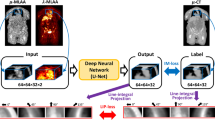

Synthetic CT generation

The sCT was generated by a deep learning algorithm from the ZTE image developed by GE Healthcare for MR-only radiotherapy. The algorithm as described previously [18, 25], consisted of a 2D convolution neural network adapted to a multi-task UNet framework. The network is trained by multiple loss functions, each designed to focus specifically on image translation, bone segmentation, and bone density value estimation. This supervised learning model was trained on co-registered pairs of ZTE and CT images from 36 pelvic radiotherapy patients (28 for model training and 8 for validation), which did not include the 10 patients in this study. The training data was augmented six-fold using random flips, zoom-in and zoom-out, in-plane and 3D rotation and the addition of Gaussian noise. The sCT algorithm was applied to PET attenuation correction without modification.

The final map used the standard vendor-supplied (GE Healthcare) patient model derived from the automatic Dixon sequence (MRAC). This method segmented the MR into four tissue classes: air, lung, fat and soft tissue, and assigned population-derived bulk density \(511\;\textrm{keV}\) linear attenuation coefficients to each class [9]. Air pockets within the patient were converted to water density automatically. Despite the MRAC being derived from the in-phase MR, the MRAC contour was slightly larger due to differences in image resolution between the DIXON and MRAC. Therefore, the MRAC was also cropped to the in-phase MR external contour to ensure all attenuation correction maps had the same external contour. Examples of the three attenuation maps are shown in Fig. 1.